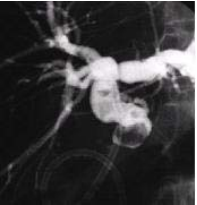

3.3.5. Chụp cộng hưởng từ mật tụy

Cộng hưởng từ mật tụy được dùng để:

- Kiểm tra các bệnh lý của gan, ống mật, túi mật, tuyến tụy như u, sỏi hay viêm nhiễm.

- Tìm nguyên nhân viêm tụy.

- Tìm nguyên nhân gây ra đau bụng.

- Sử dụng như một phương pháp chẩn đoán ít xâm lấn hơn so với nội soi đường mật ngược dòng (ERCP).

Vì vậy đây là phương pháp có giá trị chẩn đoán chính xác rất cao. Tuy nhiên có nhược điểm là chi phí tốn kém, không thực hiện được nếu có dị vật kim loại trong cơ thể.

Hình 7. Hình ảnh sỏi đường mật trên phim MRI [5]